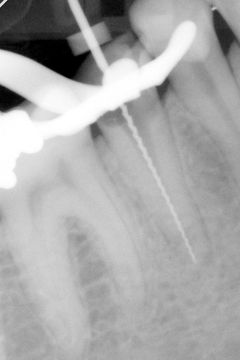

Zhotovíme digitální rentgenový snímek s kořenovým nástrojem nebo gutaperčovým čepem zavedeným v kořenovém kanálku. Vzhledem k tomu, že známe skutečnou délku zavedeného nástroje, resp. čepu, je pomocí speciální kalibrace možné kompenzovat zkreslení snímku vzniklé při focení, a díky tomu přesně změřit vybraný úsek.

měření délky kořenového kanálku pomocí radioviziografie rentgenový snímek se zavedeným nástrojem

Po změření délky kořenového kanálku a stanovení tzv. pracovní délky opracováváme kořenový kanálek nástroji se stoupajícím průměrem (u strojové techniky i stoupajícím konusem) tak, aby v místě foramen apicale vzniklo tzv. apikální stop (schůdek pro opření gutaperčového čepu při plnění kořene). Apikální stop zajistí přesné usazení čepu v požadované vzdálenosti od apexu (hrotu kořene) a brání přetlačení výplňové hmoty přes apex do přilehlé kosti.